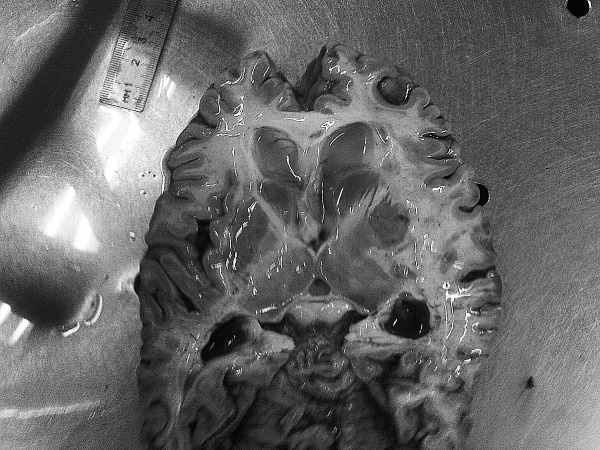

Иллюстрация к книге — Маломобильный пациент [i_037.jpg]

Иллюстрация к книге — Маломобильный пациент [i_038.jpg]

Рис. 28. Признаки болезни Альцгеймера: атрофия коры, выраженная гидроцефалия